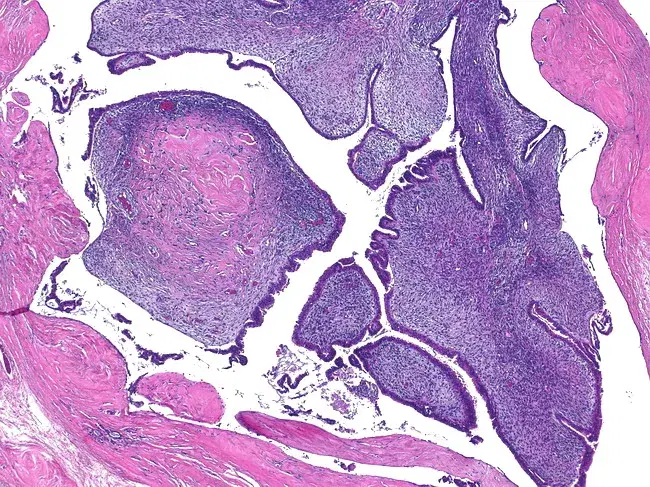

Depending on the type of growth, the histological variants of fibroadenomas are as follows:

• Pericanalicular: characterized by the growth of connective tissue around the mammary ducts while maintaining their patency;

• Intracanalicular: connective tissue growth occurs inside the duct, leading to its deformation and narrowing of the lumen up to complete occlusion;

• Mixed fibroadenoma: connective tissue growth occurs both around and inside the ducts.

Pericanalicular fibroadenoma

Pericanalicular fibroadenoma. Source: WebPathology [11]

Intracanalicular fibroadenoma.

Intracanalicular fibroadenoma. Source: WebPathology [11]

Below are histological images of low-grade phyllodes tumors (fibroadenomas) having various manifestations and histological changes. Source: WebPathology [11]: